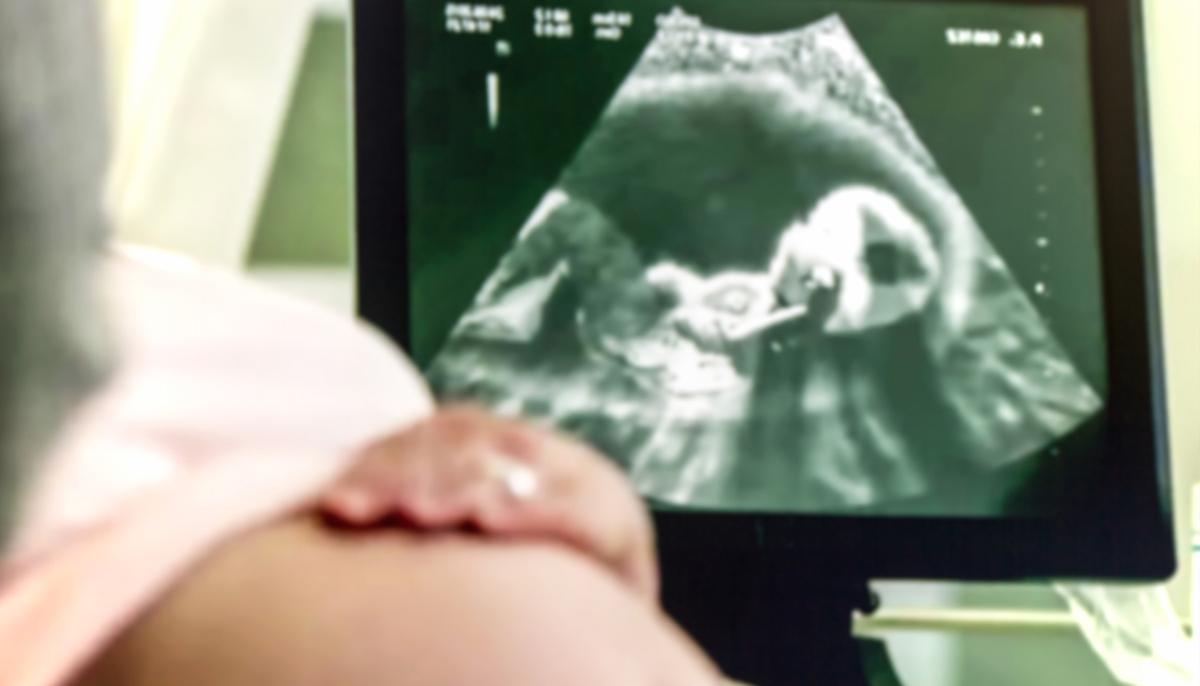

Yet another tiny town in east Texas has taken the bold step of outlawing abortion.

Although largely a symbolic act, the town of East Mountain has mustered the full force of the law to ban abortion providers from performing their services within town limits.